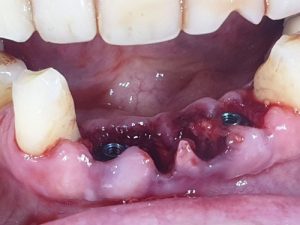

Teeth 32, 31, 41 and 42 presented with periodontitis with deep pockets and mobility, which required extractions, hence the choice of immediate loading.

Extraction, implant procedure and selection of the most suitable multi-unit for the case.